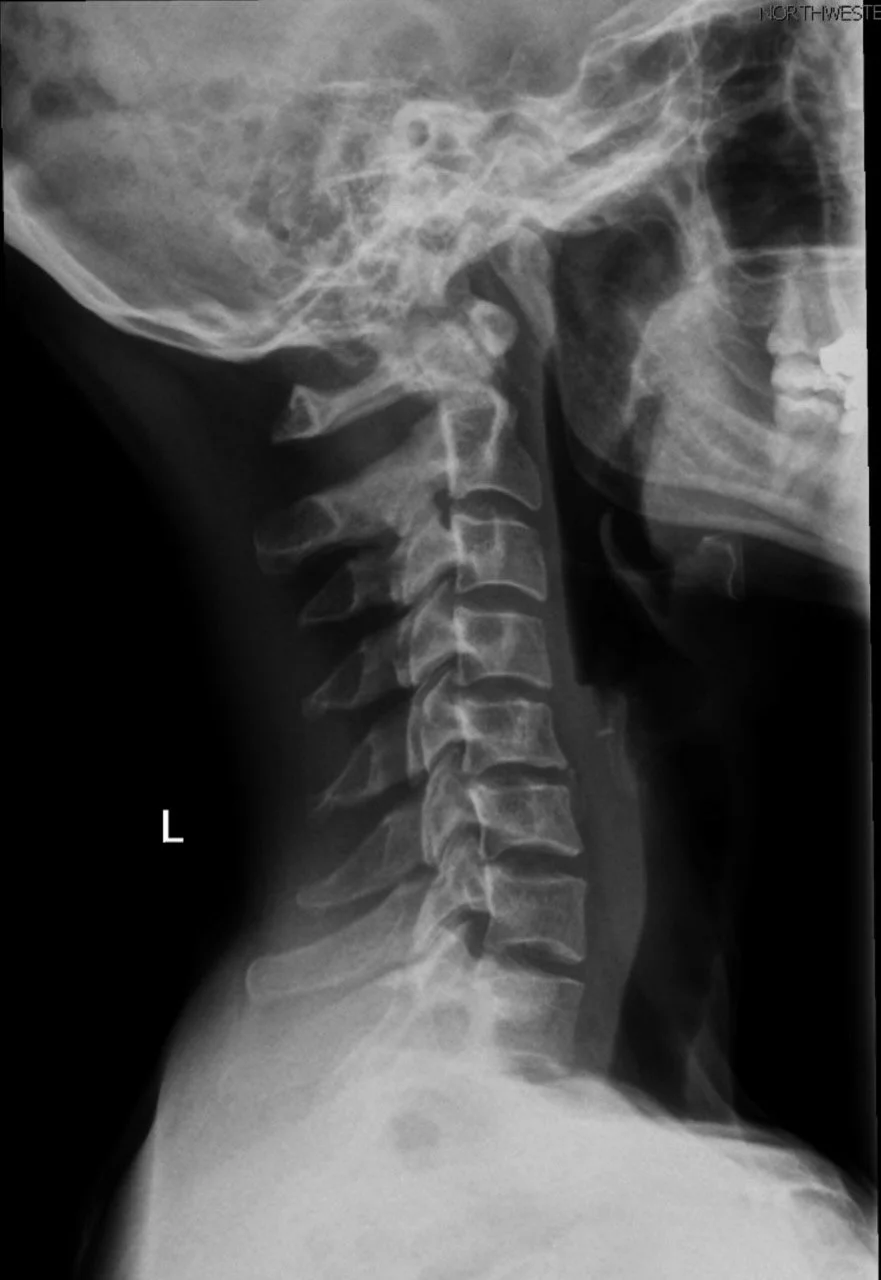

Spinal Column and Spinal Cord Spinal Column Learn More Spinal Cord Learn More Cervical Spine Learn More Lumbar Spine Learn More